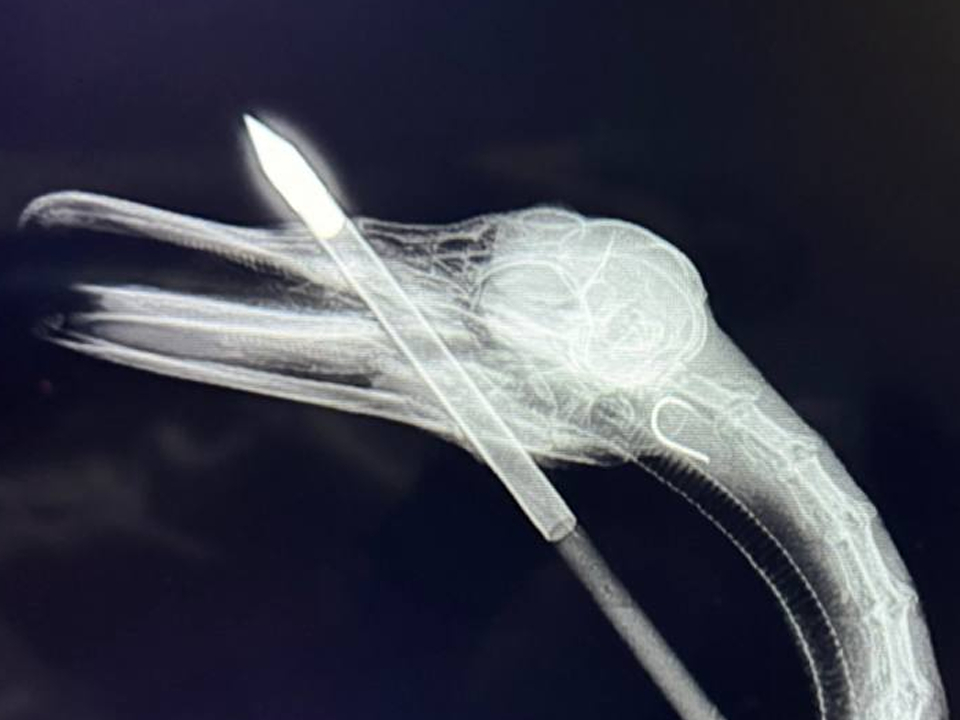

В Балашихе успешно прооперировали селезня с арбалетной стрелой в головеВ Балашихе, в клинике «Зеленый попугай», успешно прооперировали селезня с арбалетной стрелой в голове и рыболовным крючком в горле. Как рассказал REGIONS спаситель птицы орнитолог, ветеринар Иван Краснов, сейчас жизни селезня ничего не угрожает, однако, изначально прогноз был крайне неблагоприятный.

В ходе осмотра селезня специалист понял, что птица ранена стрелой, выпущенной из арбалета, также селезень был сильно истощен. После оказания первой помощи его погрузили в машину, и врач стал искать ближайшую клинику, где смогли бы провести операцию пациенту.

После обнаружения в горле птицы рыболовного крючка, Иван понял, что шансов на спасение стало еще меньше, но специалиста не остановила даже остановка сердца у селезня во время операции. Проведенная реанимация дала результат — дыхание возобновилось, операция прошла успешно.